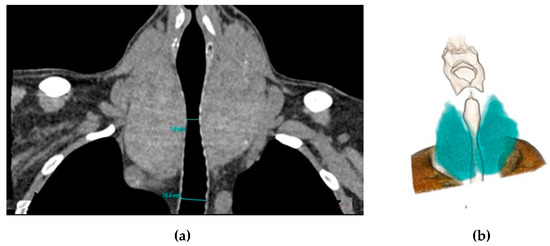

2.2.2. Image Evaluation